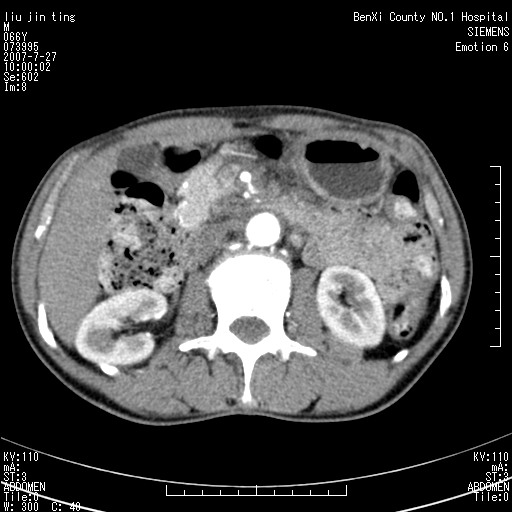

腹痛,背痛,无恶心呕吐,不黄,彩超示胰腺钩癌,ct扫描病灶平扫30-40hu,增强后动脉期40--60hu,静脉期50-68hu,真的是钩突上的么?您要试一试么?

动脉期

静脉期

沿着肠系膜上动脉呈匍匐性生长的软组织肿块,形态不规则,包绕肠系膜上动脉,呈明显强化,考虑来源于肠系膜的恶性肿瘤

沿着肠系膜上动脉呈匍匐性生长的软组织肿块,形态不规则,包绕肠系膜上动脉,呈轻-中度强化,考虑来源于肠系膜的恶性肿瘤。

钩突是正常的,只见腹膜后淋巴结的肿大,考虑淋巴瘤或转移可能。

支持!恶性纤维组织细胞瘤可能,与淋巴瘤及淋巴结转移鉴别(腹主动脉周围清晰,其他部位亦未见明显肿大淋巴结)。